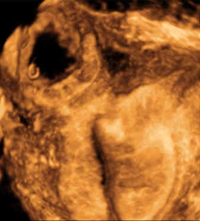

Cardiac teratoma and pericardial effusion.